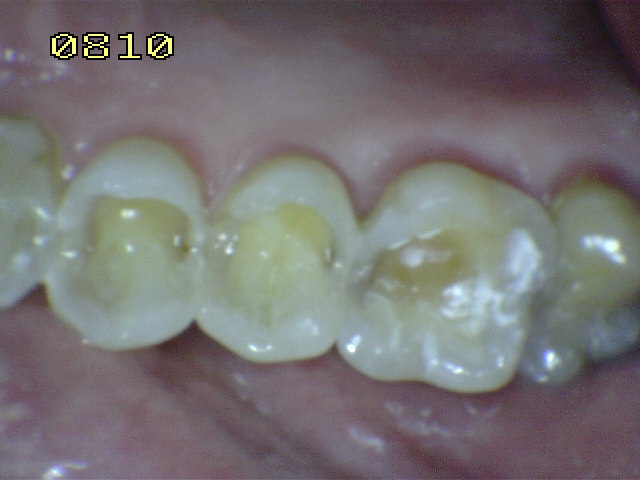

Observe el desgaste rampante de las cúspides de premolares y

molares con dentina expuesta |